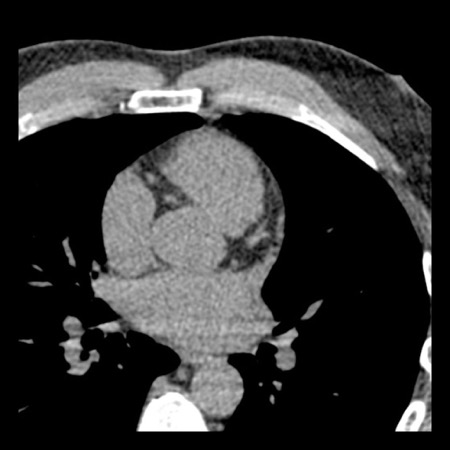

Continue with the next images of the same patient…

Same patient. First, study the CTA image.

How would you describe the findings?

The coronal image shows a central low-attenuation area around the lumen

of the LAD.

This low-attenuation area is surrounded by a higher attenuation

area.

This finding is the earlier discussed napkin-ring sign, which is a high-risk

plaque feature.

This patient classifies as CAD-RADS 4A/P1/HRP.